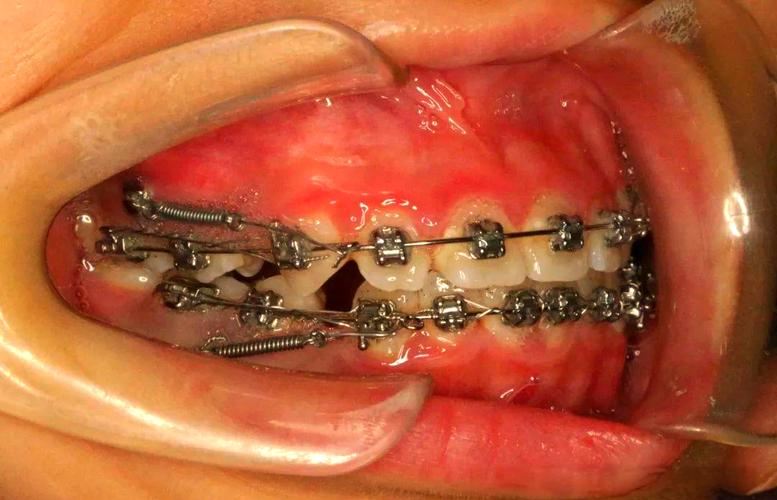

当邻牙因缺牙倾斜或对颌牙伸长导致种植空间不足时,通过矫正(如采用固定矫治器、隐形矫治器等)将倾斜的牙齿直立、伸长的牙齿压低,可恢复缺牙区的正常间隙,确保种植体直径和长度符合力学要求,为种植体提供“立足之地”,后牙缺失导致前倾的后牙侵占缺隙时,矫正需通过整体移动后牙,重建足够的骨间隙和修复空间。

矫正流程通常包括:① 口腔检查(含CBCT、模型分析);② 正畸-种植联合设计(确定矫正方案和种植体位置);③ 正畸治疗(一般1-2年);④ 保持阶段(保持器维持矫正效果);⑤ 种植手术及修复,矫正期间需定期复查,确保牙齿按计划移动,避免影响后续种植。